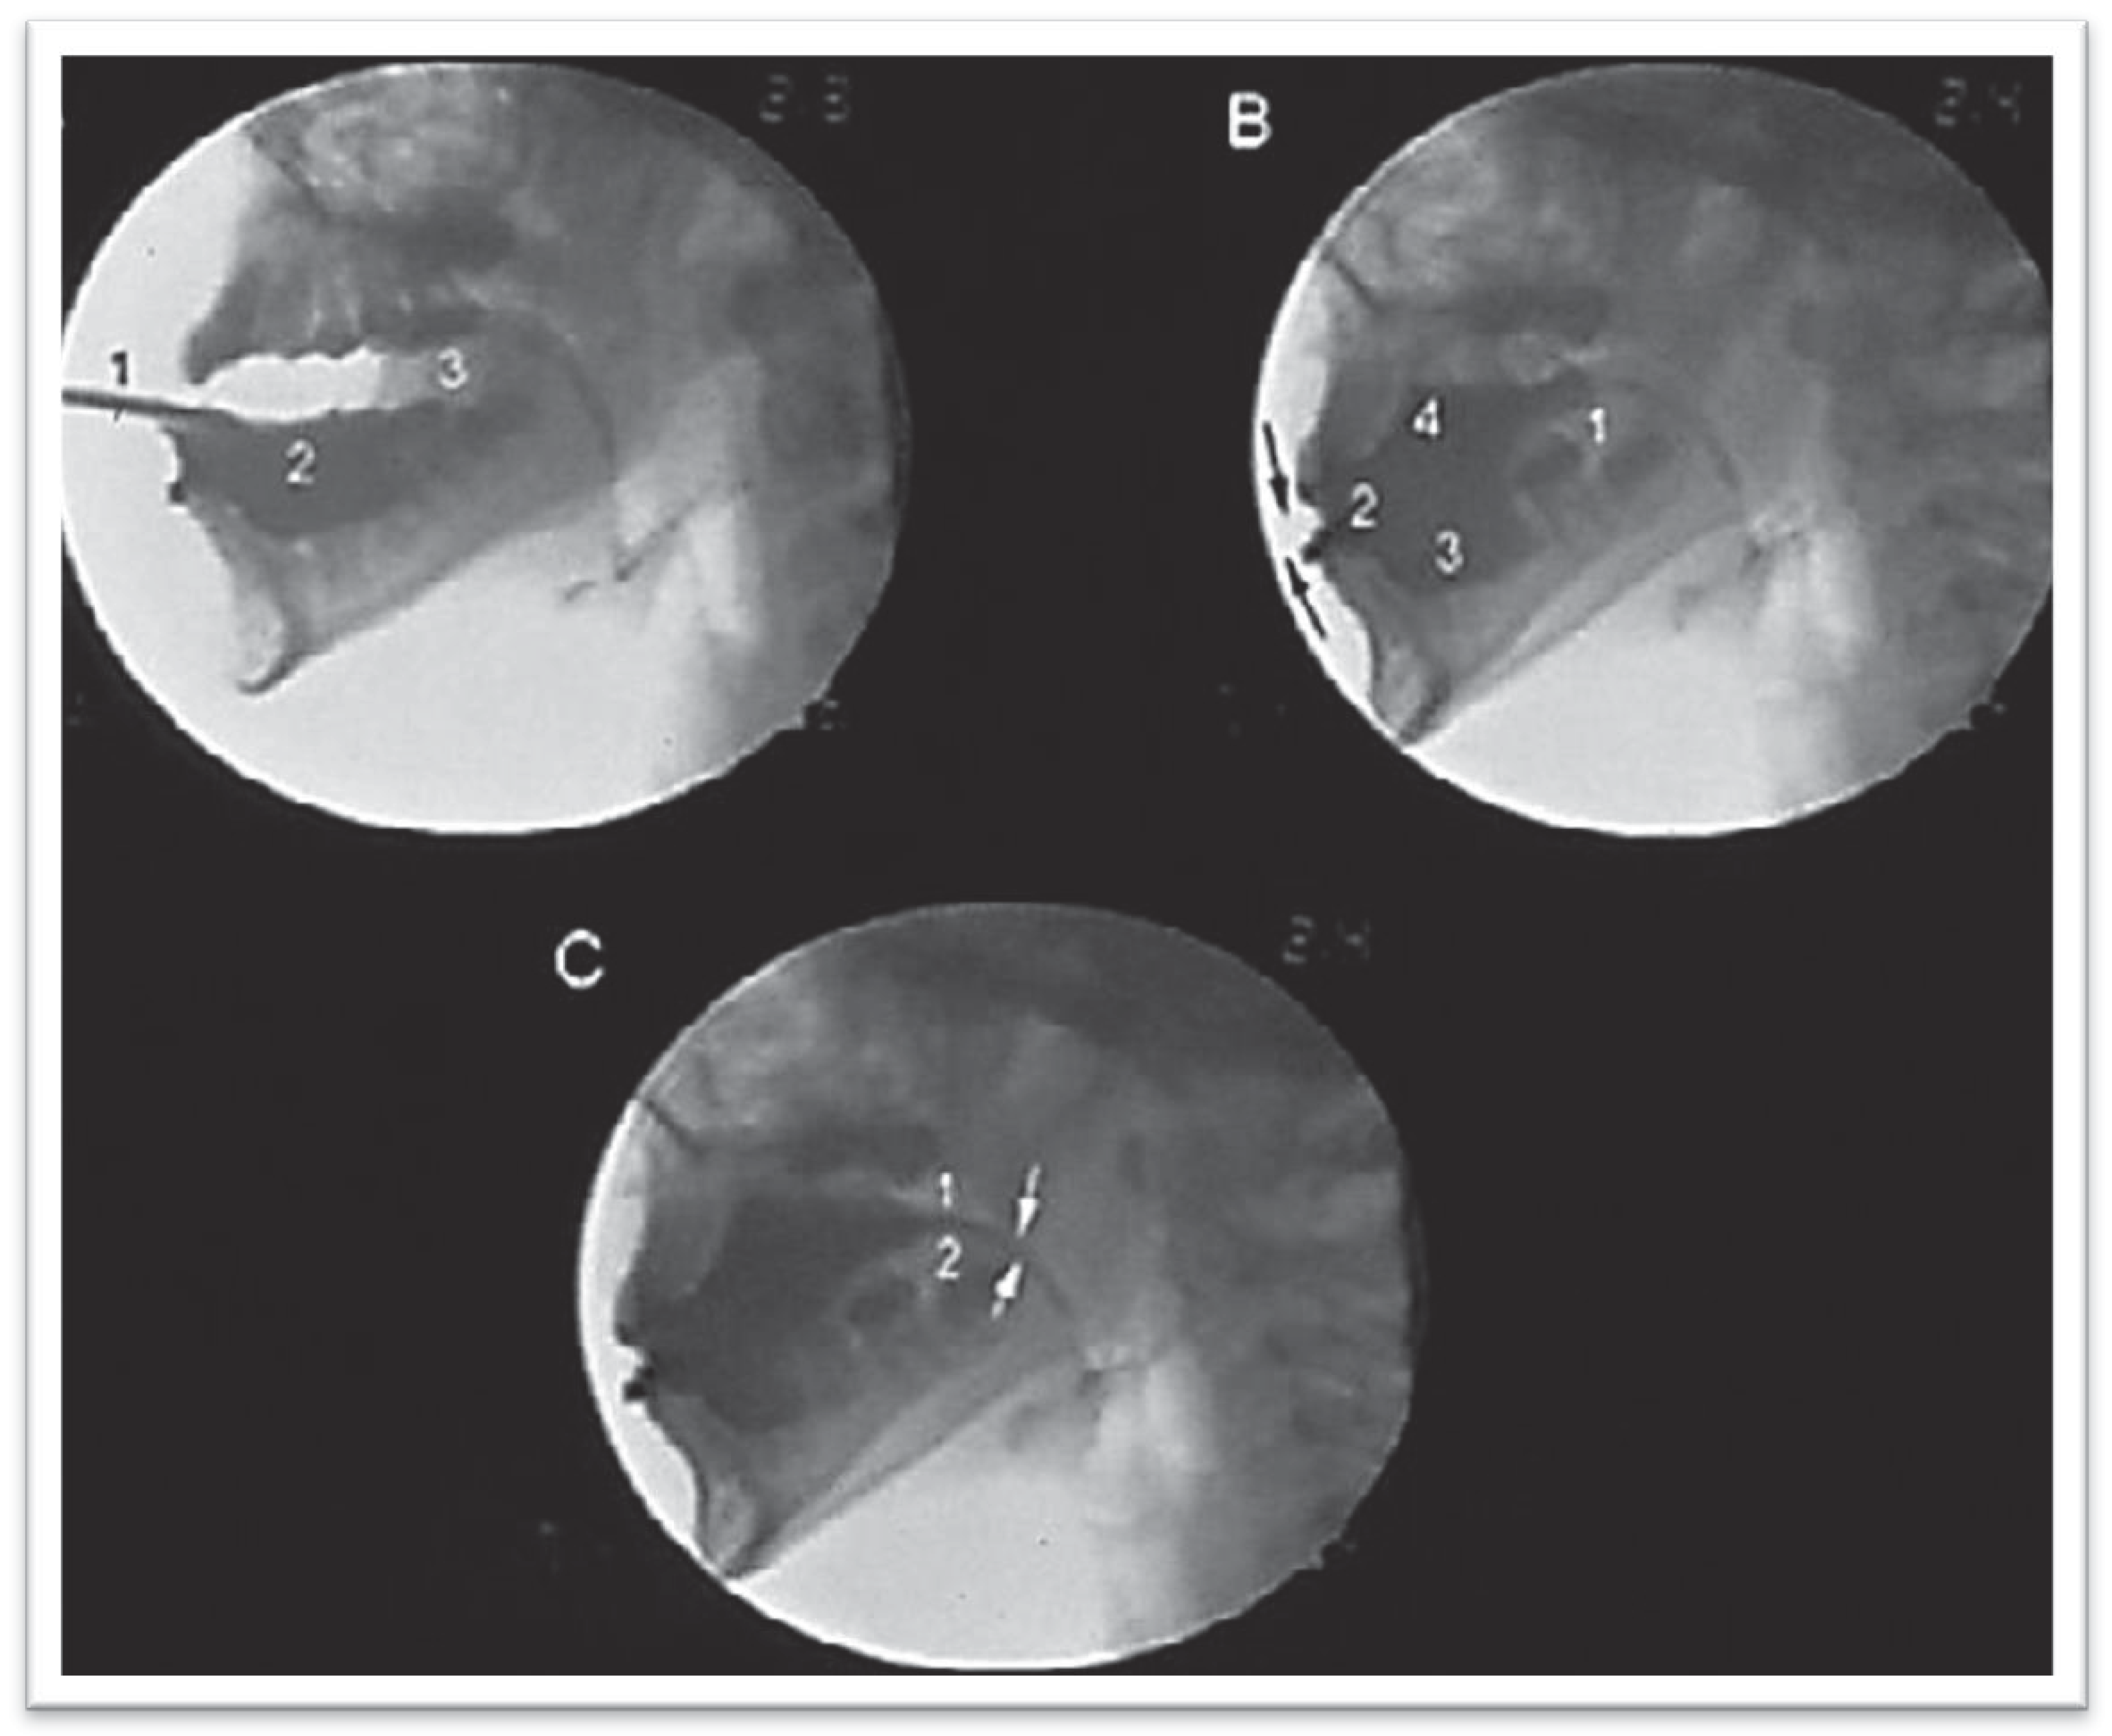

Figure 4. Videofluoroscopic exam on patient with dental malocclusion Angle Class II type, with adaptation defined as Type 3 extended during the beginning of the oral ejection phase. 1—Contrast on the dorsal surface of the tongue, starting from the anterior part of the oral cavity and 2—escaping to the oropharynx, already at the vallecula level; 3—Interposing of the tongue between the upper and lower dental arch.

Figure 5. Videofluoroscopic exam on patient with dental malocclusion Angle Class III, with adaptation defined as Type 4 Adapted Dipper. (A) 1—Admission of the contrasted solution, 2—taking anterior space, 3—generated by tongue retraction. (B) 1—Affixed lips (arrows), retracted tongue, 2—with contrasted solution taking anterior space. of the oral cavity, 3, 4—and also taking the space under and on the tongue. (C) Escape of contrast between the palate (1) and the tongue (2).